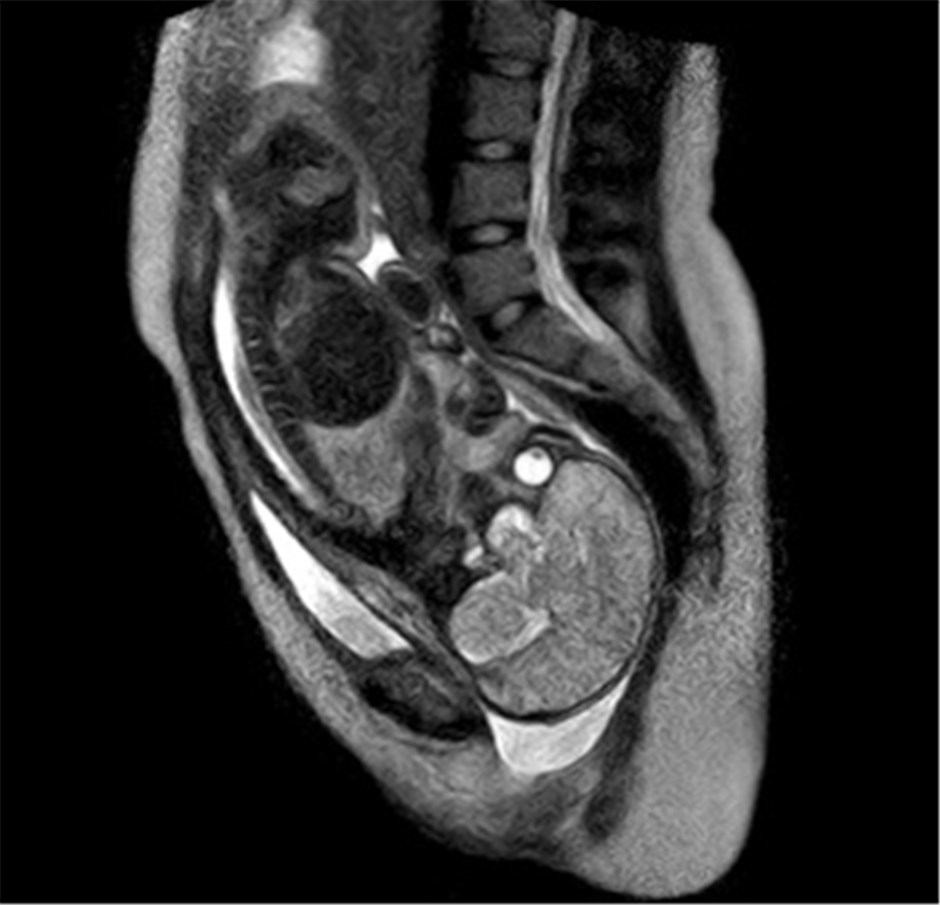

Erstmals Geburt im MRT aufgenommen MRT: Knie – DocCheck